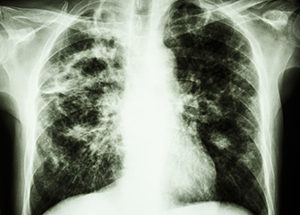

Tuberculosis (TB) is a serious disease spread through the air (usually from sneezing or coughing) from one person to another and usually affects the lungs, although can attack any part of the body.